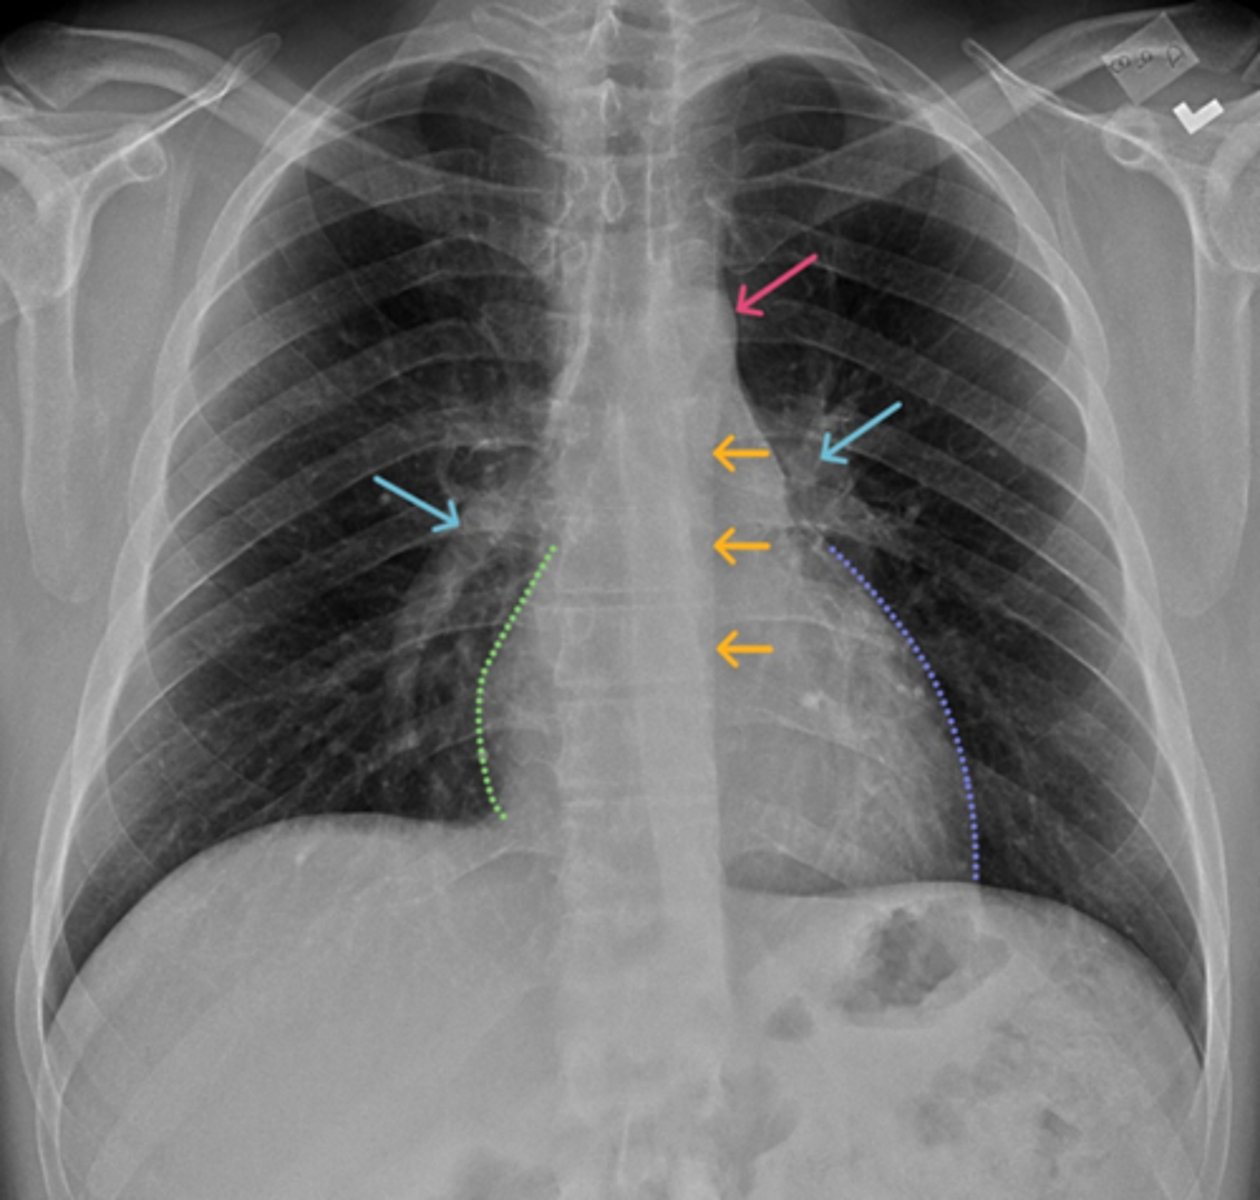

Aortic knob/arch

Pink Arrow

Left ventricle and border of the heart

Purple Line

Pulmonary arteries

Blue Arrows

Normal film

Interpretation